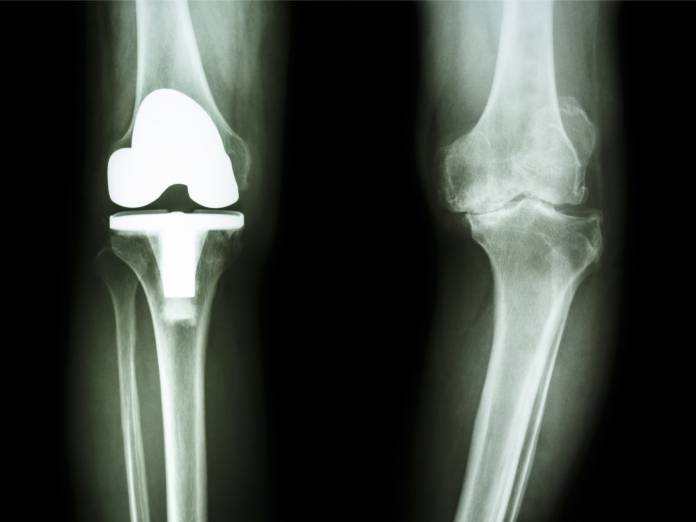

Nach einer Befragung des Patienten (Anamnese) erfolgt eine gründliche körperliche Untersuchung. Dabei kommen verschiedene Handgriffe und Untersuchungstechniken zum Einsatz. In bildgebenden Verfahren, z. B. Röntgen, Ultraschall, Computertomographie (CT) oder Magnetresonanztomographie (MRT), können Veränderungen erkannt werden. Wichtig ist in bestimmten Fällen (z. B. beim Verdacht auf Rheumatoide Arthritis) eine Blutuntersuchung. In einer Gelenkspiegelung (Arthroskopie) können krankhafte Veränderungen über ein optisches Gerät gesehen und beurteilt werden.

Zum Gelenkersatz gibt es mehrere Prothesenarten von verschiedenen Herstellern. Welche Möglichkeit gewählt wird, hängt von den individuellen Umständen ab, so unter anderem vom Zustand der Gelenkkapsel und der Bänder sowie vom Allgemeinzustand des Patienten. Meist wird eine Total-Endoprothese eingesetzt, bei der die gesamte Verbindung von Oberschenkelknochen und Schienbein erneuert wird (Knie-TEP). Nur manchmal genügt eine Teilprothese.

Die beschriebenen Prothesen können auf unterschiedliche Art und Weise eingepflanzt werden. Häufig vorgenommen wird eine zementfreie Verankerung, wenn die Prothese passgenau in den Knochen eingefügt wird. Hier dauert die Einheilung mehrere Wochen, da das Knochengewebe um die Prothese, die eine raue Oberfläche besitzt, herum wachsen muss. Möglich ist auch eine Einzementierung der Materialien mit speziellem Kunststoff (so genannter Knochenzement). Dieser verhärtet sich nach der Verarbeitung rasch, so dass das betroffene Bein bald wieder belastet werden kann. Bisweilen kommen beide Varianten an einem Kniegelenk zum Einsatz, wenn an einem Ende eine Einzementierung, am anderen Ende jedoch eine zementfreie Verankerung vorgenommen wird.